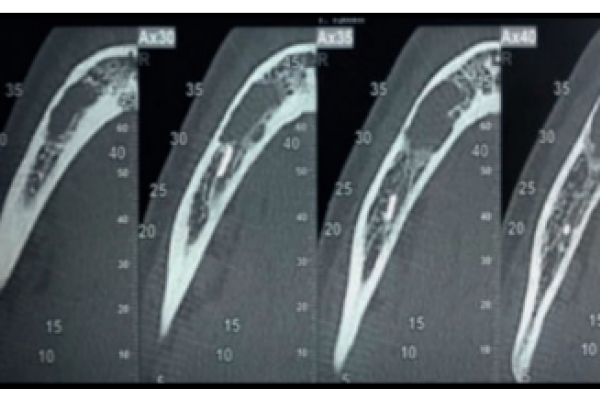

Prevención de defectos periodontales tras la exodoncia de terceros molares inferiores con injerto de dentina autógena: evaluación a 6 meses de un caso clínico